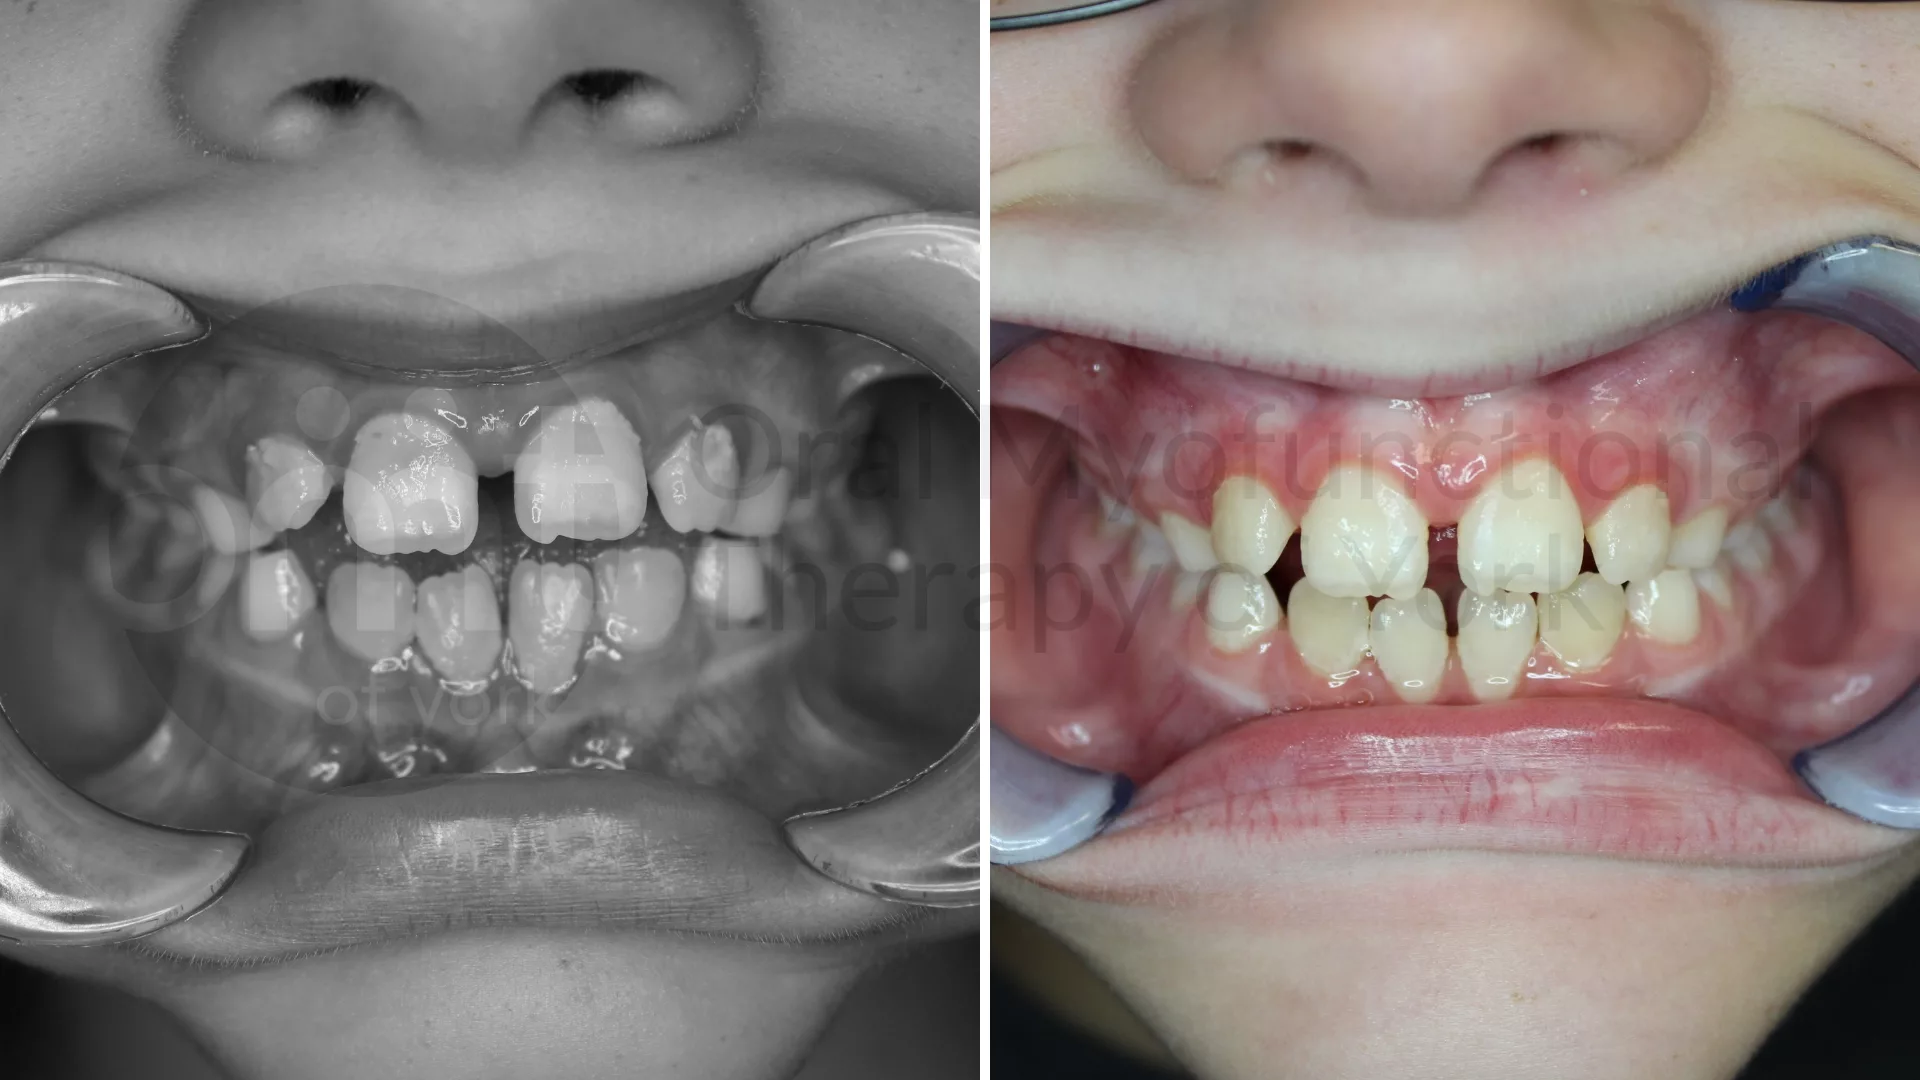

Thumb sucking elimination, therapy and a frenectomy leading to improved growth patterns

Eliminating oral habits such as thumb sucking can lead to better alignment of the teeth and jaws.

Eliminating oral habits such as thumb sucking can lead to better alignment of the teeth and jaws.